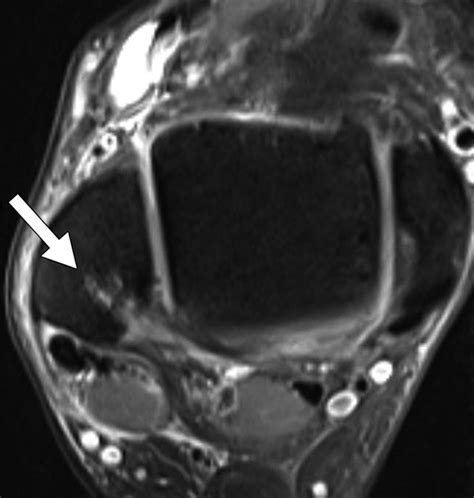

Magnetic Resonance Imaging (MRI) Offers detailed images of the bone marrow and surrounding tissues, making it the gold standard for diagnosing bone marrow edema.